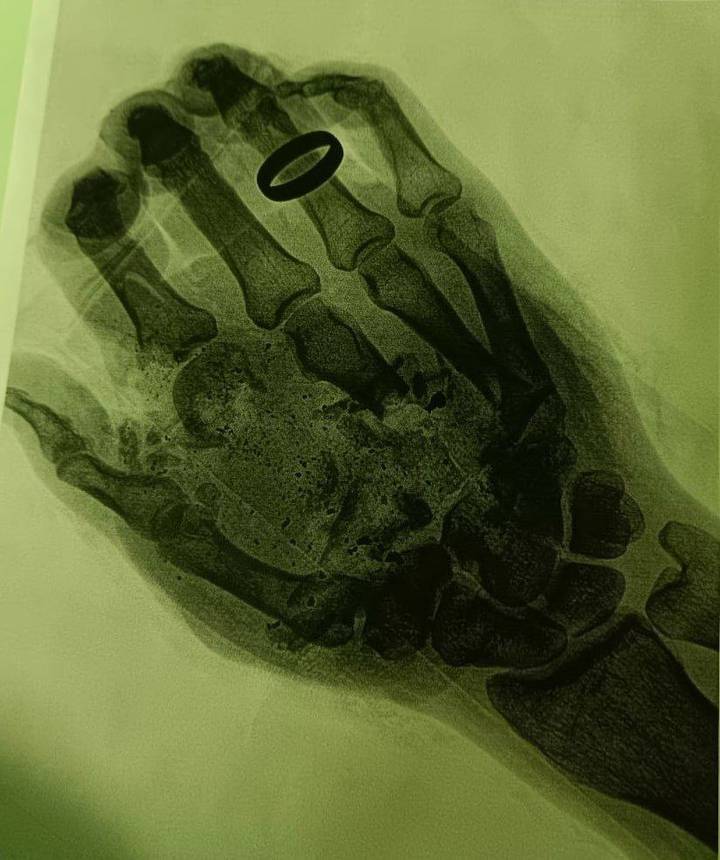

В Подмосковье мужчине раздробило руку из-за взрыва газового баллона. Об этом сообщили в пресс-службе Министерства здравоохранения Московской области в понедельник, 22 мая.

По данным ведомства, инцидент произошел в городском округе Орехово-Зуево. 36-летний мужчина отдыхал на природе, и в какой-то момент у него в руке взорвался газовый баллон. В результате хлопка кисть мужчины была серьезно повреждена. Его госпитализировали.

Мужчине раздробило руку из-за взрыва газового баллона в Подмосковье Фото: Пресс-служба Министерства здравоохранения Московской области

В отделении местной больницы пострадавшему поставили диагноз «размозжение мягких тканей кисти и фаланг пальцев». Было принято решение проводить операцию.

— Во время первого этапа мы провели тщательную обработку ран и собрали все кожные лоскуты. Затем наложили мужчине аппарат временной фиксации, — рассказал врач-травматолог-ортопед Дмитрий Лактанов.

Процедура прошла успешно, медики смогли сохранить чувствительность, микроциркуляцию и подвижность кисти пострадавшего. В данный момент мужчина чувствует себя хорошо, его выписали из больницы. Теперь жителю Подмосковья предстоит длительный процесс реабилитации.